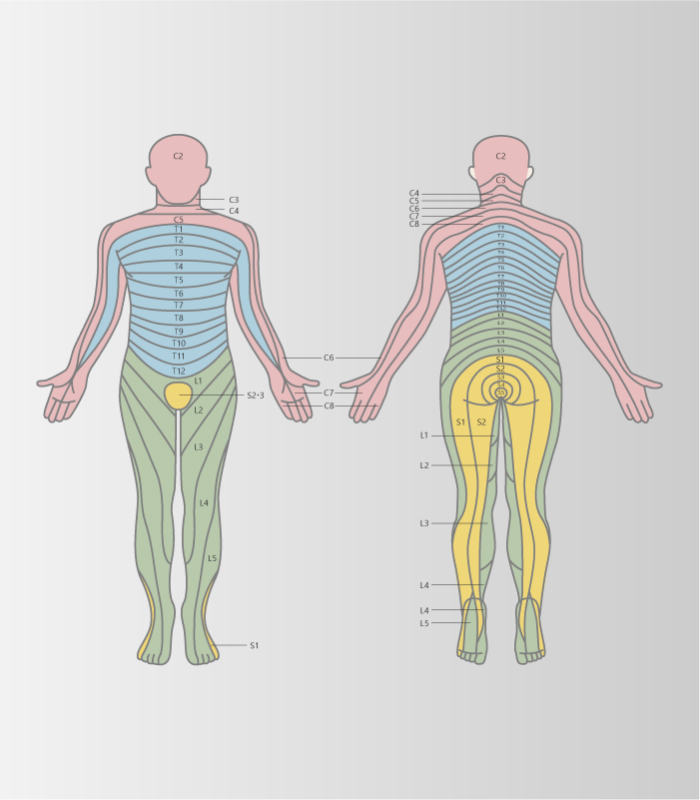

脊柱管狭窄症(神経根型/馬尾形)

-

柱管内部の変性が原因

- 腰部神経組織周囲が変性や肥厚することにより神経を圧迫する

- 間欠性跛行(閉塞性動脈硬化症との鑑別)

診断基準(日本整形外科学会ガイドライン)

- 殿部から下肢の疼痛やしびれを有する

- 殿部から下肢の疼痛やしびれは立位や歩行の持続によって出現あるいは増悪し、前屈や座位保持で軽快する

- 歩行で増悪する腰痛は単独であれば除外する

- MRIなどの画像で脊柱管や椎間孔の変性狭窄状態が確認され、臨床所見を説明できる

※4つすべて満たすと脊柱管狭窄症と診断されます。

※脊柱管狭窄症と診断されたが、上記の4項目のうち1つでも当てはまらないものがある方は、改善できる可能性があります。

頸部の神経症状

上肢のしびれ

頸部の神経症状

上肢のしびれ

-

上肢への放散痛やしびれ、感覚障害さらには運動機能障害も引き起こされることがある

頸部神経根症

頸部神経根症

上位交差性症候群

-

首の骨に負荷が継続的にかかり続けることで椎間板が変性し、骨棘を形成することよって、頚椎にある「椎間孔」が狭くなり、神経根が圧迫された刺激されて肩や腕の痛みや痺れといった症状をきたす。